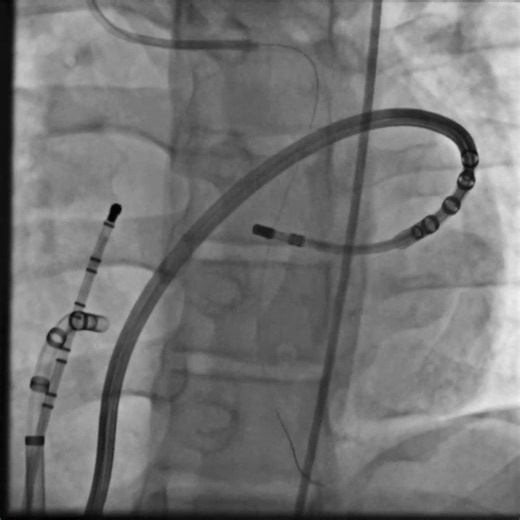

Ventricular Contractions - PVCs

- Premature Ventricular Contractions